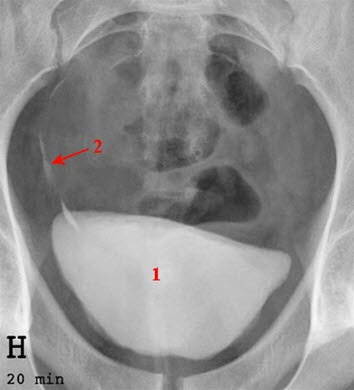

Urografi av urinblærenInterstitiell cystitt kalles også "smertefull blære syndrom" (painful bladder syndrome). Tilstanden er karakterisert ved smerter i blære og underliv og økt vannlatningstrang med hyppige vannlatninger både dag og natt. Det er typisk at smertene lindres ved vannlatning og øker når blæren fylles. Ofte føler man en unormal sterk og hurtig innsettende trang til vannlating. Plagene er langvarige, og de har en tendens til å komme og gå. Diagnosen forutsetter at man har utelukket en lang rekke andre sykdommer som kan gi liknende plager.